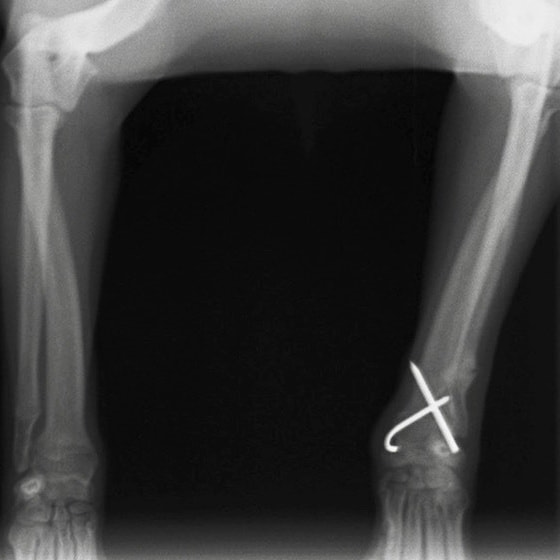

症例3:キルシュナーワイヤーのピンニングによる整復

ペルシャ猫 11ヶ月齢 雄

他院にて左大腿骨遠位の成長板骨折(salter-harrisⅠ型)が認められており、治療相談を目的として来院。当院にて、キルシュナーワイヤーを用いたピンニングにより骨折部位の整復を行いました。術後の経過は良好で、現在も経過観察中です。

術前レントゲン

術後レントゲン